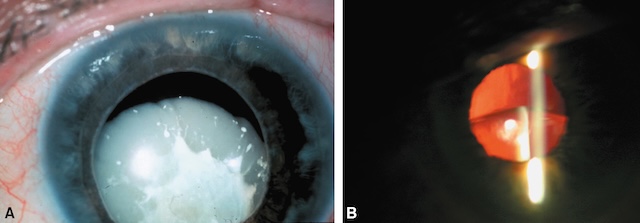

e 212Cristallin

Selon l’importance du traumatisme et la résistance des fibres de la zonule, on peut observer :

- • une subluxation du cristallin (fig. 11.6) ou une luxation incomplète avec rupture partielle de la zonule;

Fig. 11.6 A, B. Subluxation et opacification du cristallin. L’image A montre un cristallin opacifié en position subluxée. Il apparaît en partie déplacé vers le haut, avec une capsule blanchâtre, irrégulière et totalement opaque, rendant impossible la visualisation du fond d’œil. L’iris reste visible, mais légèrement étalé, témoignant de la perte de centrage. L’image B, obtenue en biomicroscopie avec éclairage en fente, confirme la subluxation : le cristallin, à la forme irrégulière, laisse passer un faisceau lumineux oblique, dévié par la densité du noyau. Le reflet rouge du fond d’œil est partiellement visible, limité par l’opacité cristallinienne. Ces signes évoquent une luxation partielle avec cataracte évoluée.

- •

une luxation complète du cristallin dans la chambre antérieure (fig. 11.7) ou dans la cavité vitréenne par rupture totale de la zonule;

Fig. 11.7 Luxation du cristallin dans la chambre antérieure. L’image montre un cristallin totalement luxé vers l’avant, situé dans la chambre antérieure. Sa surface arrondie et opaque repose directement contre la face postérieure de la cornée, refoulant l’iris en arrière. L’aspect bombé, grisâtre et dense du cristallin évoque une opacification évoluée, empêchant la visualisation du fond d’œil. La sclère périphérique est légèrement injectée, témoignant d’une irritation oculaire. L’angle irido-cornéen paraît fermé, ce qui peut favoriser une élévation rapide de la pression intraoculaire. Cette configuration impose une prise en charge chirurgicale rapide pour prévenir les complications glaucomateuses ou cornéennes.

une cataracte contusive (apparaissant plusieurs semaines ou mois après le traumatisme).